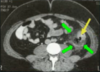

TOMOGRAFIA DE ABDOMEN COM CONSTRASTE VENOSO .

MASSA RETROPERITONEAL A DIREITA QUE COMPRIME AS VISCERAS A DIREITA , A QUAL NÃO INVADE AS ESTRUTURAS. PRESENÇA DE CAPTAÇÃO HETEROGENEA DO CONSTRASTE NA PERIFERIA

ASPECTO DE SARCOMA PERITONEAL.